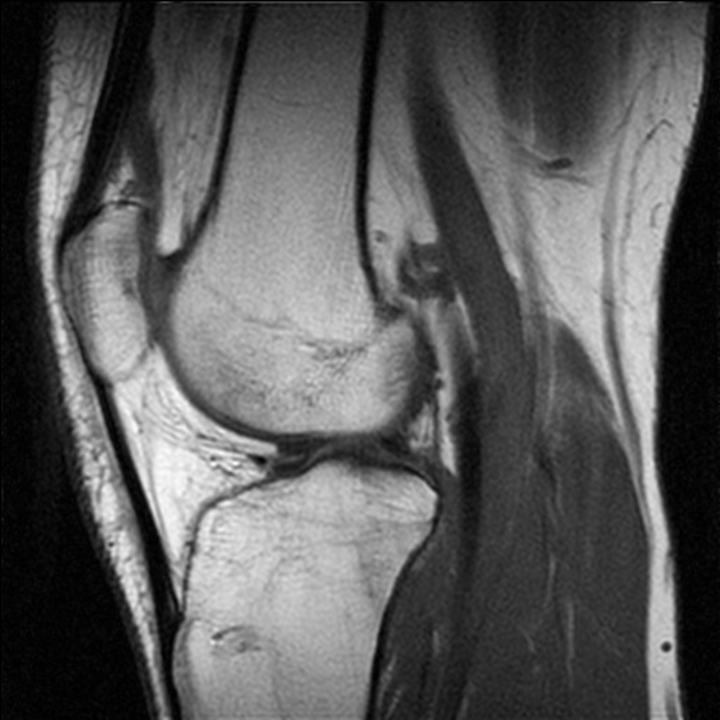

РОЗПІЗНАЙТЕ ДОДАТКОВІ ЕЛЕМЕНТИ ЦЬОГО СПОЛУЧЕННЯ.

варіанти відповідей

ДИСКИ

МЕНІСКИ

СУМКИ

БУРСИ

ЗВ'ЯЗКИ